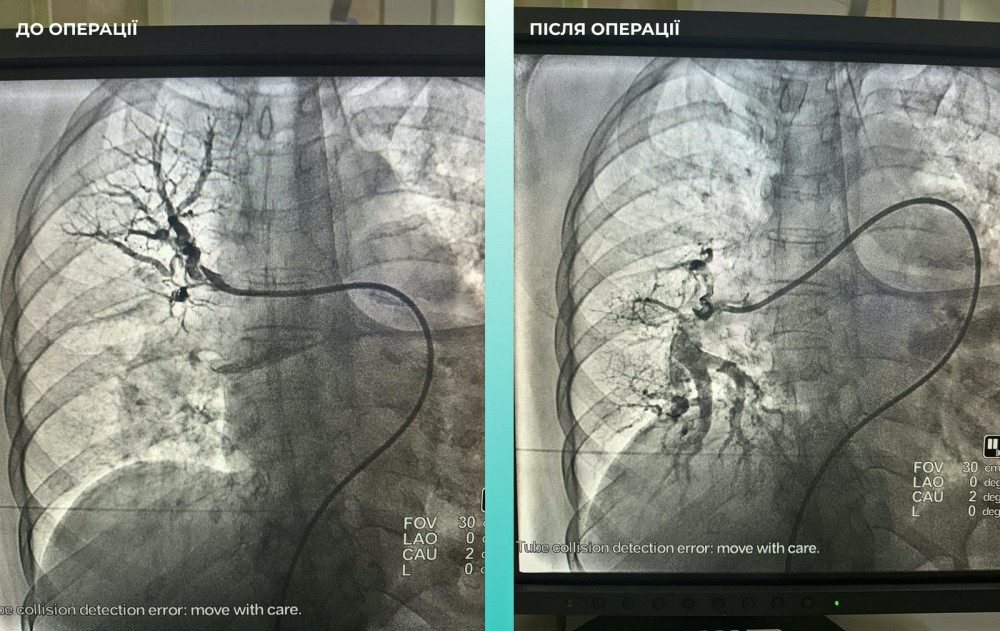

Мультидисциплінарна команда спеціалістів прийняла важливе рішення — провести одночасну тромбектомію в мозковій та легеневій артеріях.

Операція пройшла успішно. Наразі пацієнтка почувається значно краще: вона в свідомості та може рухати кінцівками.